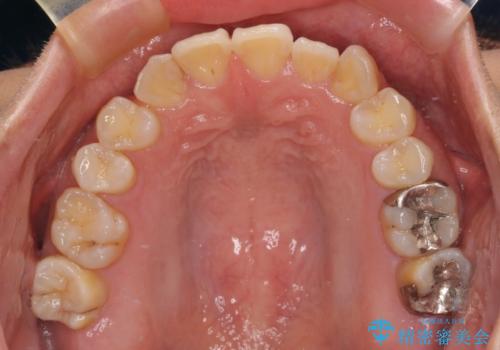

マウスピース矯正が煩わしい ワイヤー装置での非抜歯矯正

上下前歯のデコボコを気にして来院された患者様です。

舌の突出癖により、治療過程でスペースが多くできましたが、舌のトレーニングを頑張っていただき、1年強で終えることができました。